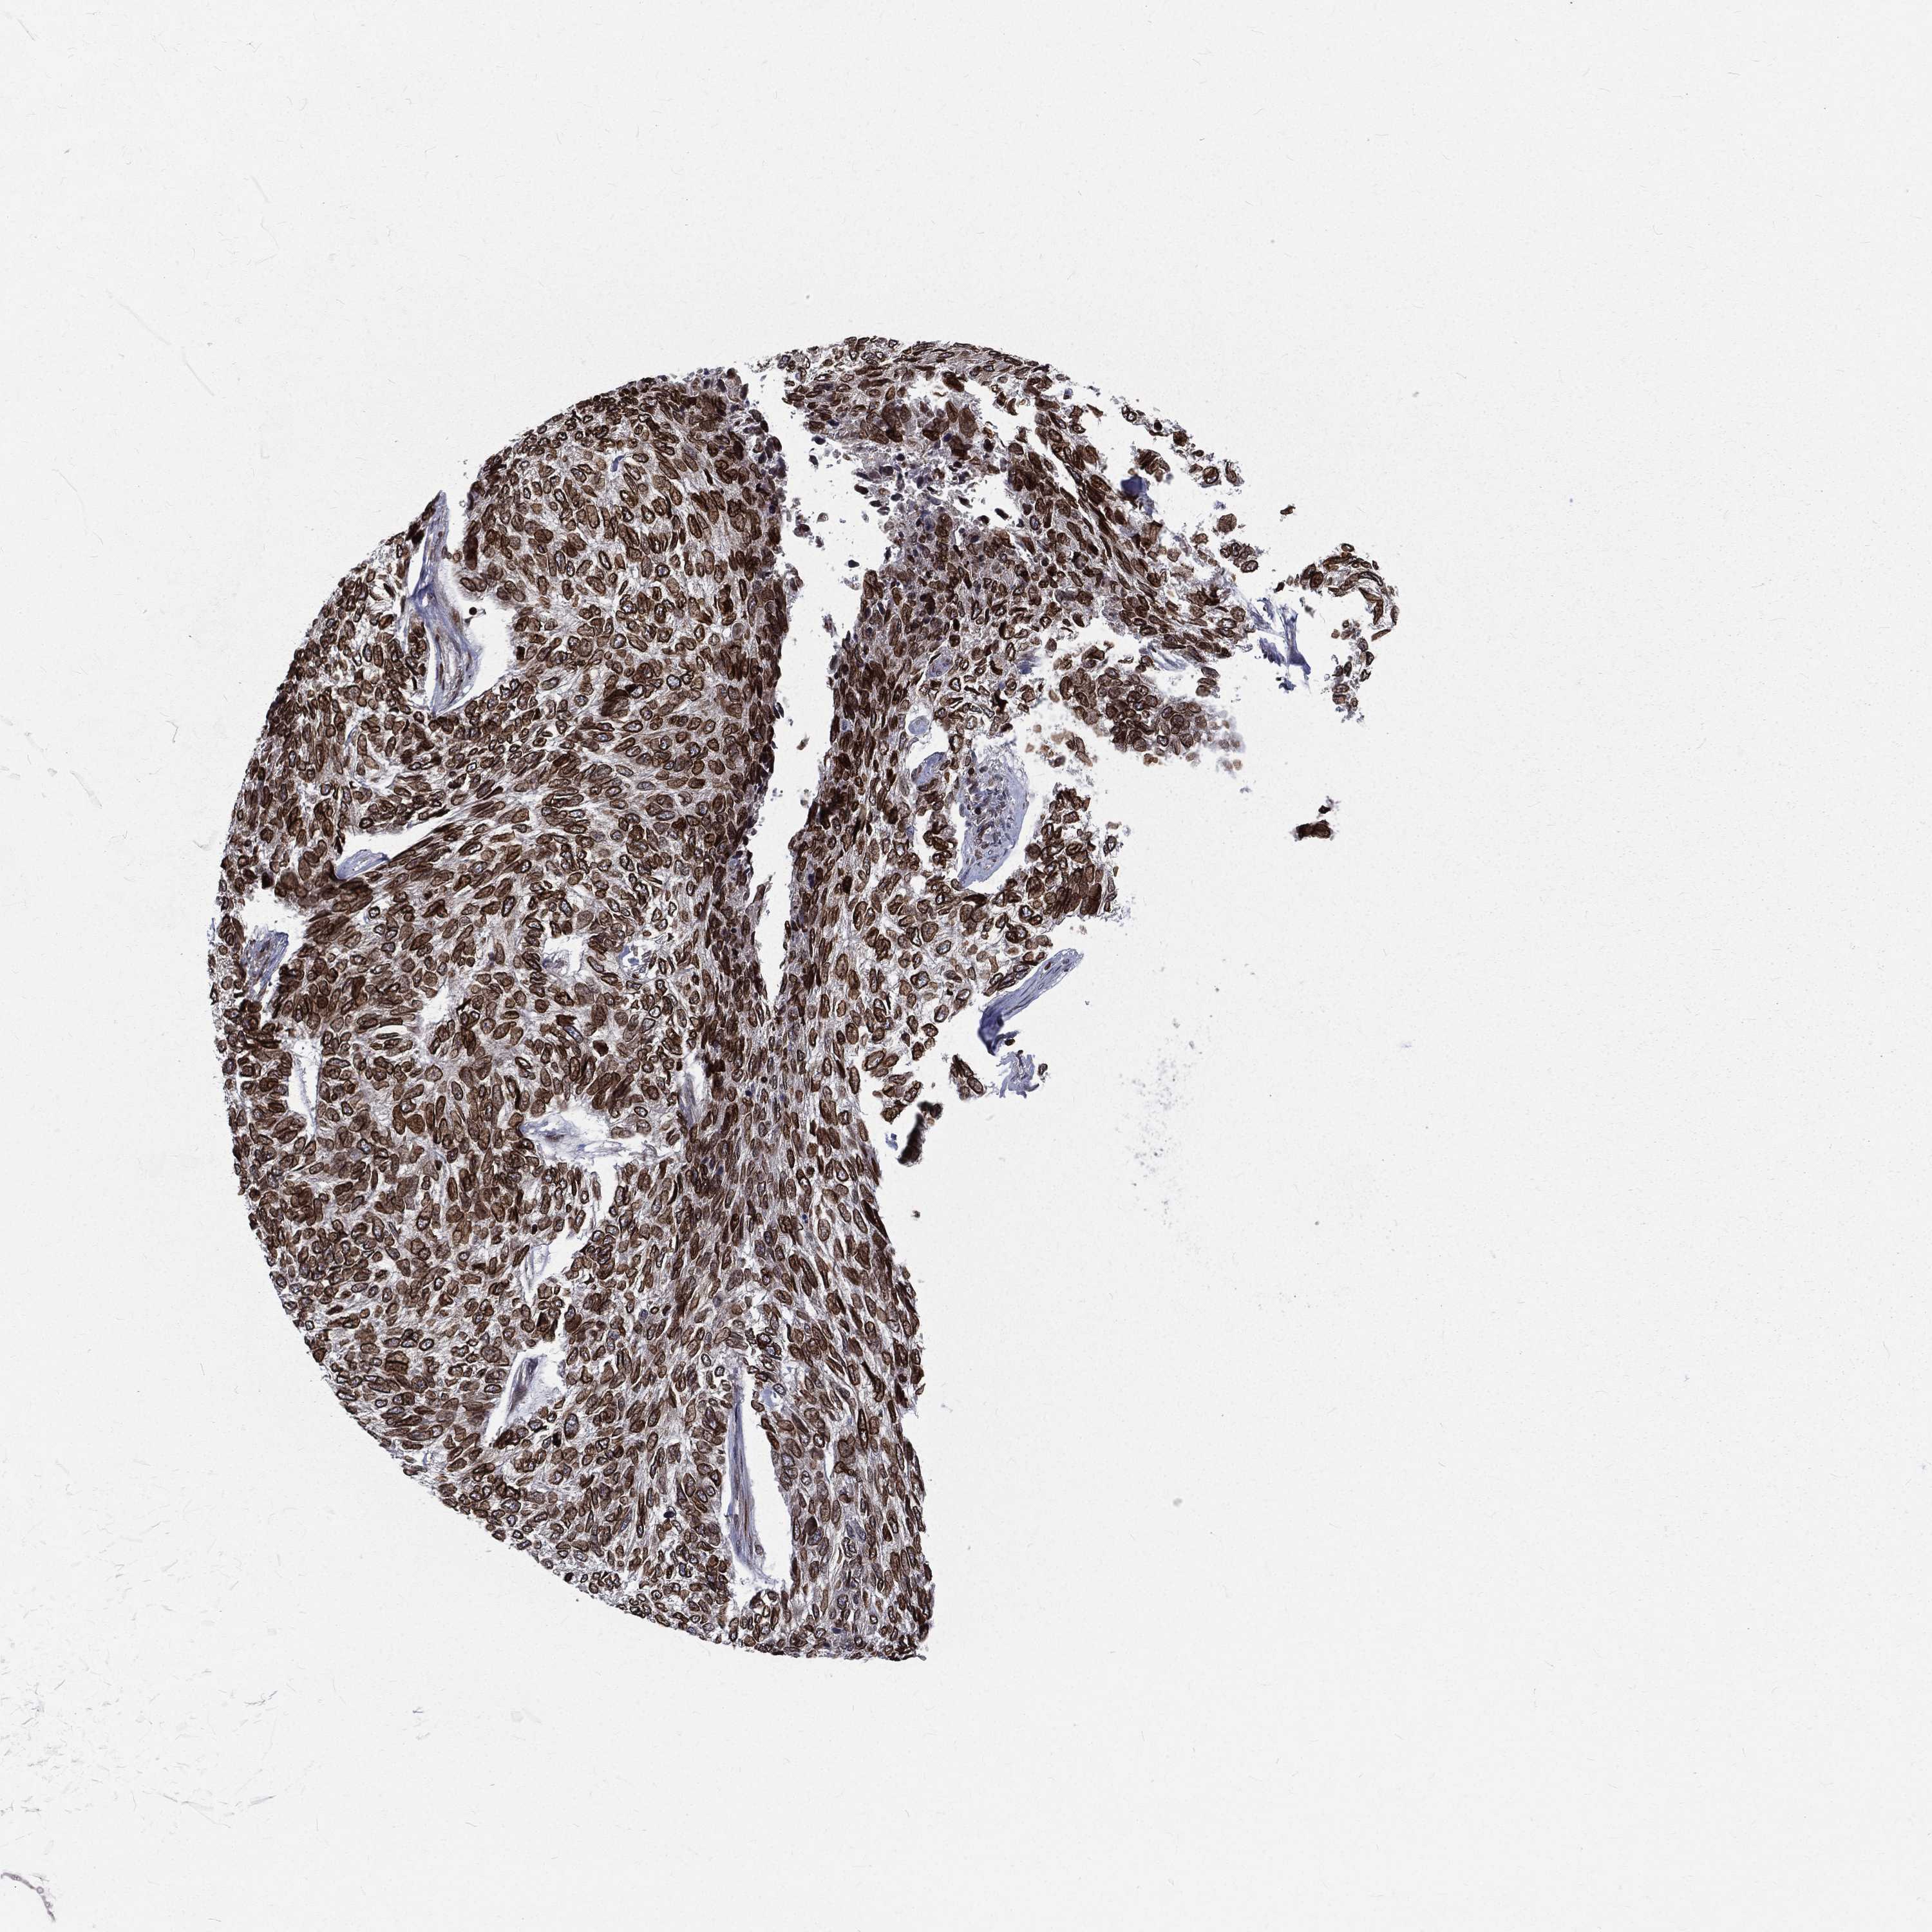

Basal cell and squamous cell cancer

SKIN CANCER - Protein expressioni

A mouse-over function shows sample information and annotation data. Click on an image to view it in a full screen mode. Samples can be filtered based on level of antibody staining by selecting one or several of the following categories: high, medium, low and not detected. The assay and annotation is described here.

Antibody stainingi

Antibody staining in the annotated cell types in the current human tissue is reported as not detected, low, medium, or high, based on conventional immunohistochemistry profiling in selected tissues. This score is based on the combination of the staining intensity and fraction of stained cells.

Each image is clickable and will lead to virtual microscopy that enables deeper exploration of all samples and also displays staining intensity scores, fraction scores and subcellular localization as well as patient and tissue information for each sample.

Antibody HPA049840

Staining

High

Intensity

Strong

Quantity

>75%

Location

Nuclear

Basal cell carcinoma